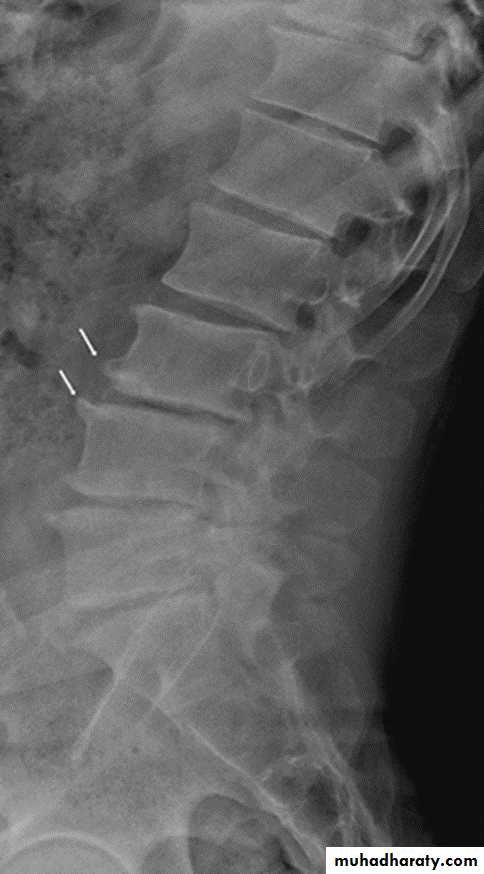

In the Spine :

* Lower cervical and low lumbar spine are most comonly affected.* Osteophytes may encroach on neural foramina (best seen on oblique views).

*Vacuum phenomenon: gas (N2),is pathognomonic of the degenerative process.

* OA of the spine occurs in the apophyseal joints .

* Degenerative spondylolisthesis (pseudospondylolithesis)

Lumbar spondylosis. There is distal narrowing and a vacuum

phenomenon is present in the degenerative discs. Marginal osteophytes arepresent. Inferiorly the facet joints show features of degeneration and, with the increase in lordosis, the spinous processes are in contact